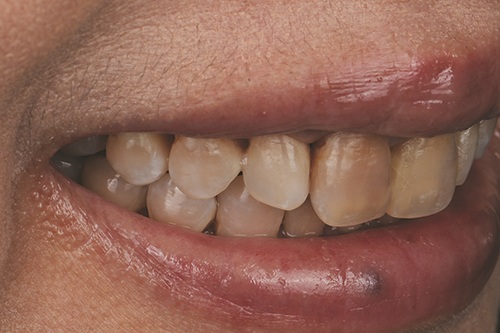

Advancements in digital manufacturing have enabled the fabrication of highly precise, ultra-thin restorations that minimize or eliminate the need for tooth reduction. This case report describes the aesthetic management of a 49-year-old patient with severe tetracycline staining (Figs. 1–3), using a no-prep approach and 3D-printed zirconia veneers. A fully digital workflow was employed, including intraoral scanning, virtual smile design (Fig. 4), and additive fabrication of 120-µm (0.12mm) zirconia shells (Figs. 5–7), to achieve a conservative aesthetic outcome while preserving natural tooth structure.

Fig. 1: Pre-op full face photo

Fig. 2

The patient presented with concerns of long-standing, generalized tooth discoloration. Despite multiple previous attempts with both at-home and in-office bleaching treatments, there was no significant improvement in the tetracycline staining resulting from prior antibiotic exposure.

Discoloration caused by tetracycline exposure from childhood. The patient was happy with her smile and the natural shape of her teeth, but desired a conservative solution to lighten the color of her “dark teeth.”

The patient presented with generalized intrinsic discoloration consistent with moderate to severe tetracycline staining, characterized by grayish-brown horizontal banding across the anterior dentition. Given the etiology of tetracycline-induced staining, originating from deep within the dentin and enamel matrix, conventional whitening treatments are typically insufficient for achieving satisfactory aesthetic outcomes. The patient’s primary objectives were to enhance the aesthetic appearance of her smile, preserve natural tooth structure, and maintain flexibility for potential revision in the future. To address these goals, 3D-printed zirconia veneers were selected as a minimally invasive option with masking characteristics suitable for intrinsic discoloration.